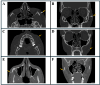

Foreign body removal in the facial region poses significant challenges due to the complex anatomy and the proximity to critical structures. This study introduces a soft tissue-borne patient-specific guide (PSG) designed to enhance precision and minimize invasiveness in foreign body removal. Four patients underwent foreign body removal using PSGs, with CT and cone-beam computed tomography (CBCT) imaging employed for segmentation and detailed analysis of both hard and soft tissues. This approach enabled the planning and design of stable and personalized guides. Ultrasound tracing was used for intraoperative verification. All procedures were successful, with minimal scarring, no complications, and reduced operative time. The use of PSGs improved surgical accuracy and efficiency, highlighting their potential for foreign body removal in other regions of the body and for broader clinical applications in maxillofacial surgeries.